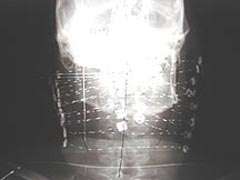

Salvage Case: This is a radiograph of an interstitial implant for a recurrent cancer in the oropharynx. The patient had previously received external beam radiation therapy. CET physicians were asked to perform salvage brachytherapy. Catheters were inserted to treat both sides of the neck and the posterior oropharynx. The radiation doses were shaped so that the spinal cord dose was not exceeded. This is achieved by the high level of dose control possible with the HDR brachytherapy system.